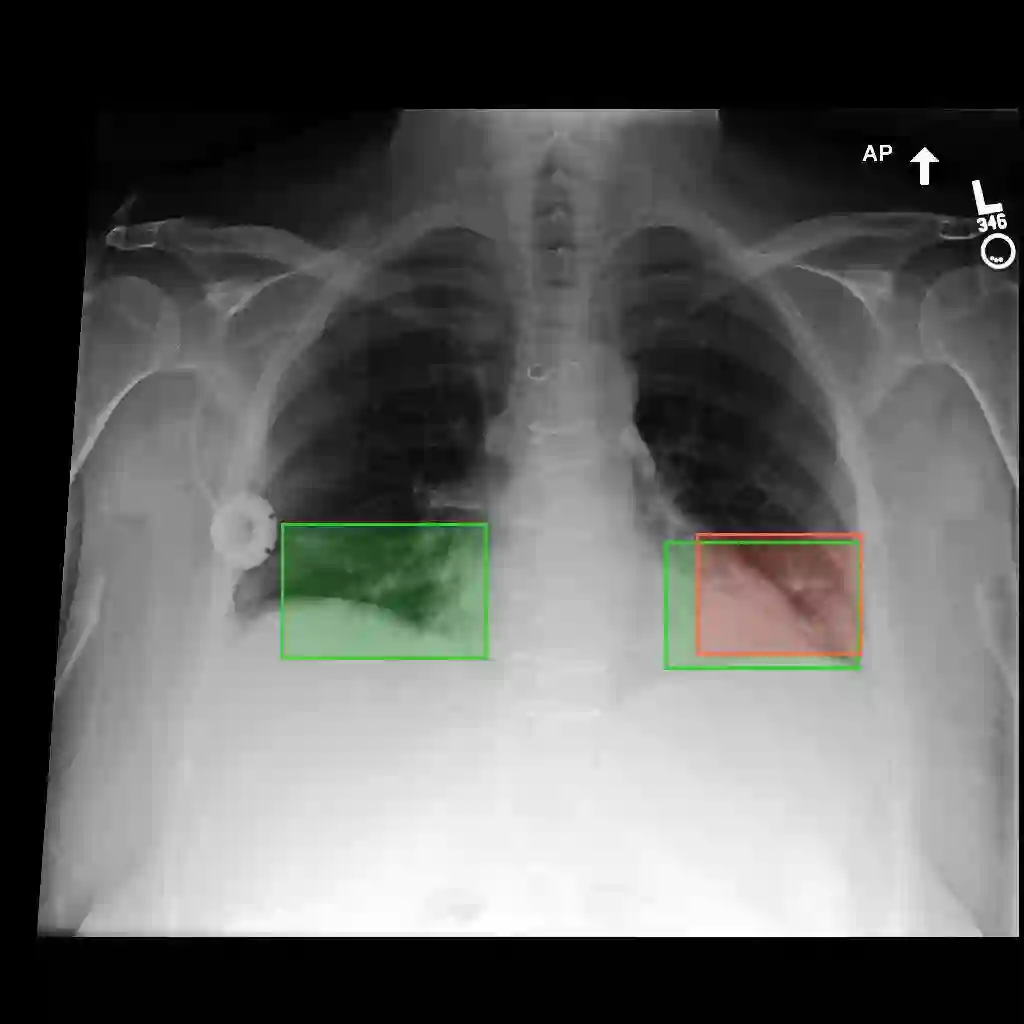

Multimodal medical large language models have shown impressive progress in chest X-ray interpretation but continue to face challenges in spatial reasoning and anatomical understanding. Although existing grounding techniques improve overall performance, they often fail to establish a true anatomical correspondence, resulting in incorrect anatomical understanding in the medical domain. To address this gap, we introduce AnatomiX, a multitask multimodal large language model explicitly designed for anatomically grounded chest X-ray interpretation. Inspired by the radiological workflow, AnatomiX adopts a two stage approach: first, it identifies anatomical structures and extracts their features, and then leverages a large language model to perform diverse downstream tasks such as phrase grounding, report generation, visual question answering, and image understanding. Extensive experiments across multiple benchmarks demonstrate that AnatomiX achieves superior anatomical reasoning and delivers over 25% improvement in performance on anatomy grounding, phrase grounding, grounded diagnosis and grounded captioning tasks compared to existing approaches. Code and pretrained model are available at https://github.com/aneesurhashmi/anatomix